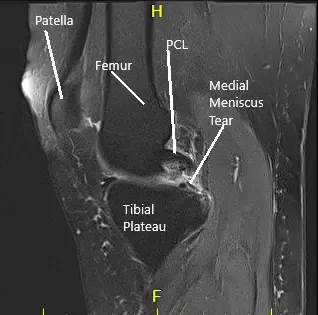

La resonancia magnética de la rodilla derecha sugirió desgarro del menisco medial y artritis patelofemoral de la rodilla derecha.

Se estableció un portal de entrada lateral y se examinó la articulación de la rodilla. Se encontró un desgarro periférico del menisco medial. También se encontró una lesión osteocondral de grado 1 a grado 2 en el cóndilo medial del fémur. El ligamento cruzado anterior presentaba algo de desgaste y degeneración.

No había lesión en el menisco ni en el fémur lateral ni en el cóndilo. Se inspeccionó la articulación patelofemoral y se encontró en buen estado. Ahora se realizó la reparación del menisco medial. Se usaron suturas FasT-Fix. Se utilizaron siete suturas para fijar la rotura periférica desde el cuerno posterior hasta la mitad del cuerpo.